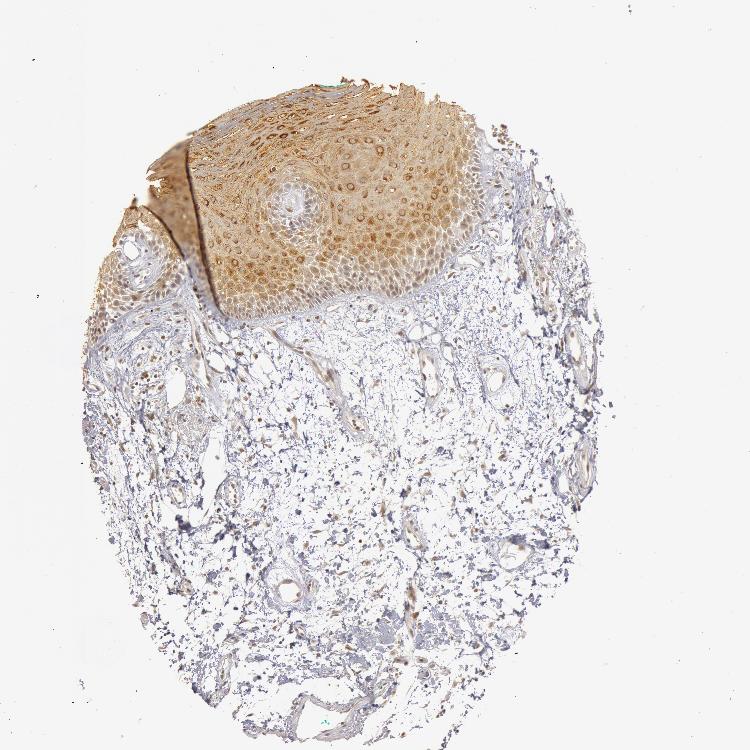

TISSUE PRIMARY DATA ORAL MUCOSA Show tissue menu

ORAL MUCOSA - Antibody stainingi

Antibody staining in the annotated cell types in the current human tissue is reported as not detected, low, medium, or high, based on conventional immunohistochemistry profiling in selected tissues. This score is based on the combination of the staining intensity and fraction of stained cells.

Each image is clickable and will lead to virtual microscopy that enables deeper exploration of all samples and also displays staining intensity scores, fraction scores and subcellular localization as well as patient and tissue information for each sample.

Antibody HPA001474

Squamous epithelial cells Medium